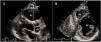

Measurement of epicardial adipose tissue thicknessAll included patients underwent detailed two-dimensional (2D), M-mode, Doppler, and tissue Doppler transthoracic echocardiography using standard techniques before beginning metformin monotherapy and after three months of treatment. The echocardiograms were performed by two experienced cardiologists who were blinded to the subjects’ clinical and demographic data. Each subject underwent 2D-guided M-mode transthoracic echocardiography using commercially available equipment (Aplio 500, Toshiba, Irvine, CA). Standard parasternal and apical views were obtained in left lateral decubitus position. EAT was visualized as echo-free space between the outer wall of the myocardium and the visceral layer of the pericardium (Figure 1). EAT thickness was measured perpendicularly on the free wall of the right ventricle during three cardiac cycles at end-diastole. Parasternal long- and short-axis views provided the most accurate measurement of EAT in the right ventricle, with optimal cursor beam orientation in each view. Maximum EAT thickness was measured at the point on the free wall of the right ventricle along the midline of the ultrasound beam perpendicular to the aortic annulus, used as an anatomic landmark for this view. For midventricular parasternal short-axis assessment, maximum EAT thickness was measured on the right ventricular free wall along the midline of the ultrasound beam, perpendicular to the ventricular septum at midchordal and tip of the papillary muscle level, as anatomic landmarks. The mean values from three cardiac cycles in each echocardiographic view were analyzed.

EAT thickness was significantly decreased after three months of metformin monotherapy (EAT0= 5.07±1.33 mm vs. EAT3=4.76±1.32 mm; p<0.001) (Figure 2).